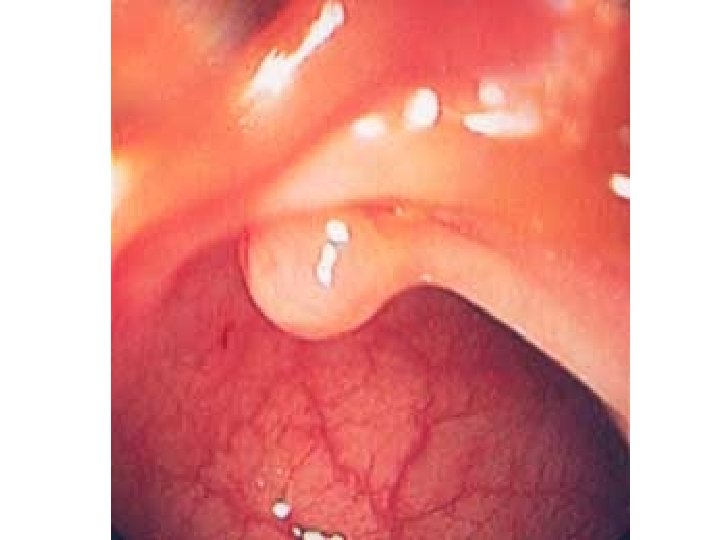

Leukoplakie – doprovázena benigním zvětšením dásně

Papilom jazyka